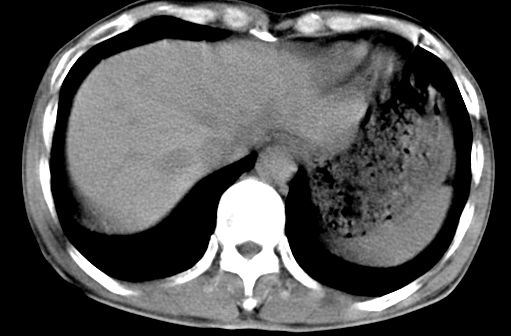

病人资料:男,50岁,上腹部隐痛,消瘦乏力,有乙肝病史二十余年,b超提示肝内内占位。

由于是基层医院,机器速度跟不上,增强效果差,请各位老师也看看!

增强动脉期应该没有捉到,可能病灶强化密度已下降了,支持考虑肝癌

肝右叶后段低密度灶,增强受机器限制,特点不明显,无等密度充填及周围强化,结合病人乙肝史20年,首先考虑肝癌。

肝右后叶占位,增强时期没抓好,特点不明显,结合病史首先考虑原发性肝癌

肝右叶后段占位,肝癌可能性大。下腔静脉无移位。肾上腺占位不支持?